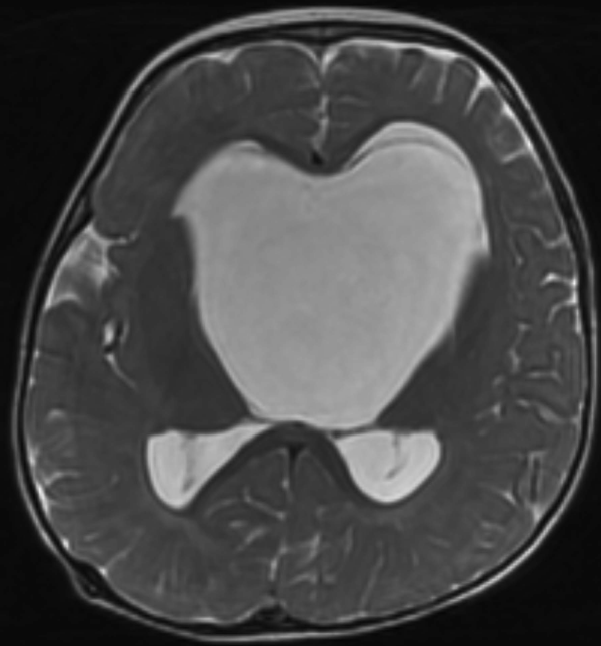

图2:脑室内蛛网膜囊肿引起阻塞性脑积水